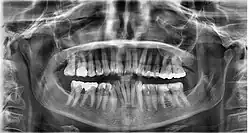

Orthopantomogramm eines Wechselgebisses

Ein Orthopantomogramm (OPT oder OPG, seltener OPTG), auch Panoramaschichtaufnahme (PSA) genannt, ist eine zweidimensionale Röntgenaufnahme des Ober- und Unterkiefers in Form eines Halbkreises von einem Ohr zum anderen. Es ist ein Standardverfahren der dentalen Radiographie und erlaubt eine diagnostische Röntgenaufnahme der Ober- und Unterkiefer des Menschen, dabei werden alle Zähne, die angrenzenden Kieferbereiche, beide Kiefergelenke und ebenso die rechte und die linke Kieferhöhle abgebildet. Das OPT erfasst ferner den seitlichen Halsbereich, so dass auch Arterienverkalkungen der großen Halsschlagadern diagnostizierbar sind.

In erster Linie dienen OPG-Aufnahmen der Übersicht, demnach einer Grobdiagnostik, beispielsweise ob Zähne verlagert, retiniert oder nicht angelegt sind. Auch Veränderungen des Kieferknochens sind erkennbar und oft der Verlauf des Nervus mandibularis. Zahlreiche Nebenbefunde können erfasst werden. Der mittlere Bereich der Aufnahme wird durch eine verfahrenstechnisch bedingte Überprojektion der Halswirbelsäule speziell im Frontzahnbereich verschattet. Ebenso werden oft die Wurzelspitzen durch eine Überprojektion des knöchernen Gaumens verschattet. Dadurch sind diese Bereiche undeutlich abgebildet und einer präzisen Diagnostik nicht zugänglich.[6]